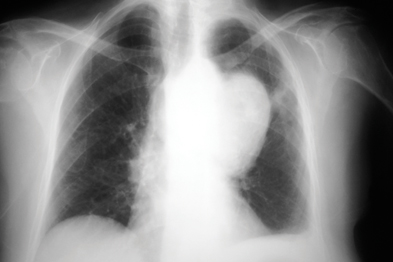

Small Cell Lung Cancer Chest X Ray

Lung Cancer - Small Cell - Symptoms And Signs

Lung Cancer

An x-ray of the chest can show tumours as small as 1cm wide. Small cell lung cancer has often spread outside the chest when it is diagnosed. It is staged in two ways: • Limited disease: is when the tumour can be detected in only ... Read Document

SMALL CELL LUNG CANCER - Home - Lung Cancer Alliance

Small Cell Lung Cancer (SCLC) may not be visible on a normal chest X-ray. PET (positron emission tomography) scans show how areas of the body patients, if the cancer is found very early, is small and has not spread to lymph nodes; ... Read Full Source

Lung Cancer - RadiologyInfo.org

Lung cancer forms in tissues of the lung, Small-cell lung cancer abnormalities using up to 90 percent less ionizing radiation than a standard chest CT scan. Chest x-ray: An x-ray exam will allow your doctor to see your lungs, ... Doc Viewer

LUNG CANCER - Napa Valley College

Staging of Lung Cancer. Non-Small Cell Lung Carcinoma. Stage 0: Chest x-ray of normal appearance taken from the back of an adult male. Non-Small Cell Lung Carcinoma. Large central lesion diagnosed as non-small cell carcinoma. Non-Small Cell Lung Carcinoma. ... Fetch Doc